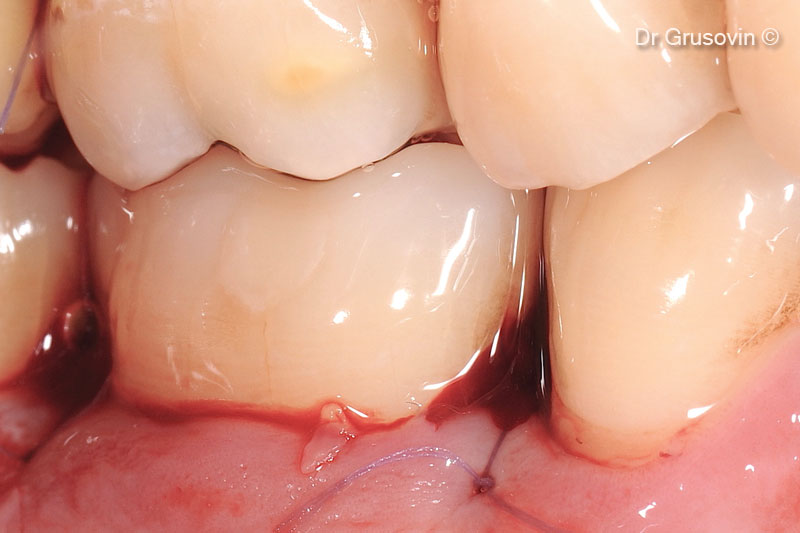

Khâu đóng vạt bảo tồn nhú

OsteoBiol® Gen-Os® được sử dụng để lấp đầy khuyết tật hai thành. Nhú lợi không bị nâng lên.

Phương pháp đóng một vạt da duy nhất